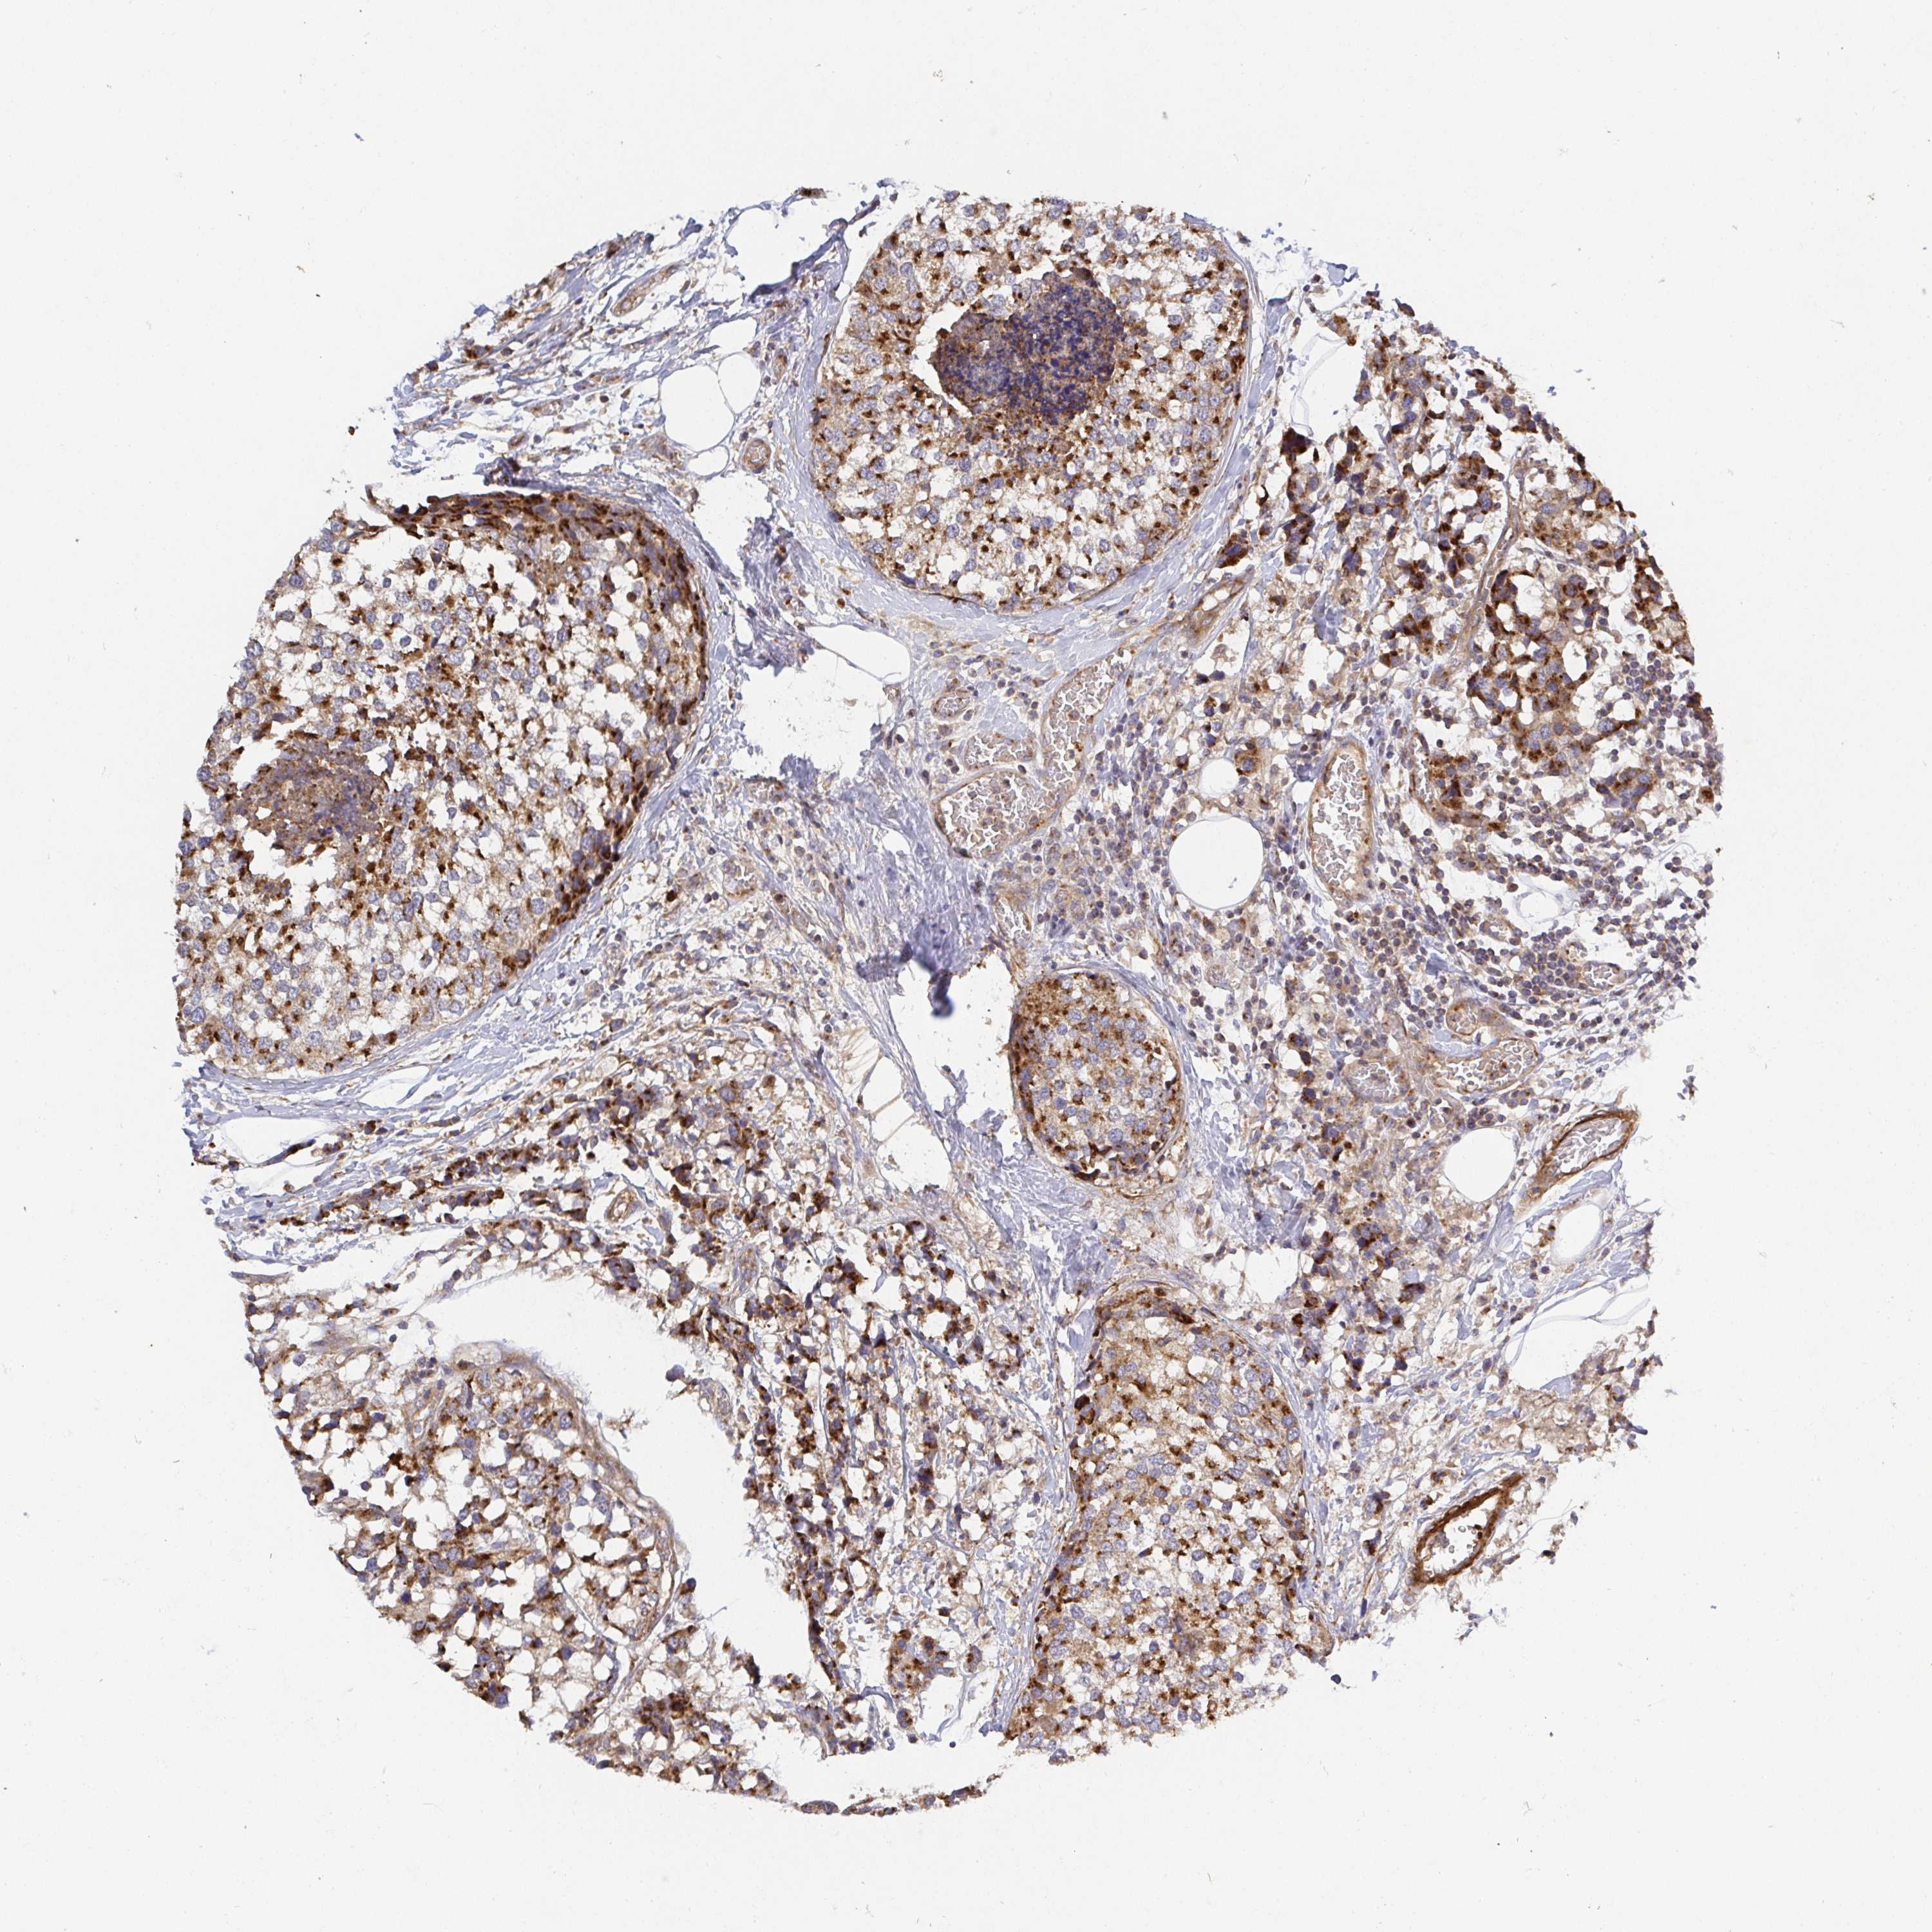

CANCER BREAST CANCER Show tissue menu

BRCA TCGA BRCA VALIDATION PROTEIN EXPRESSION